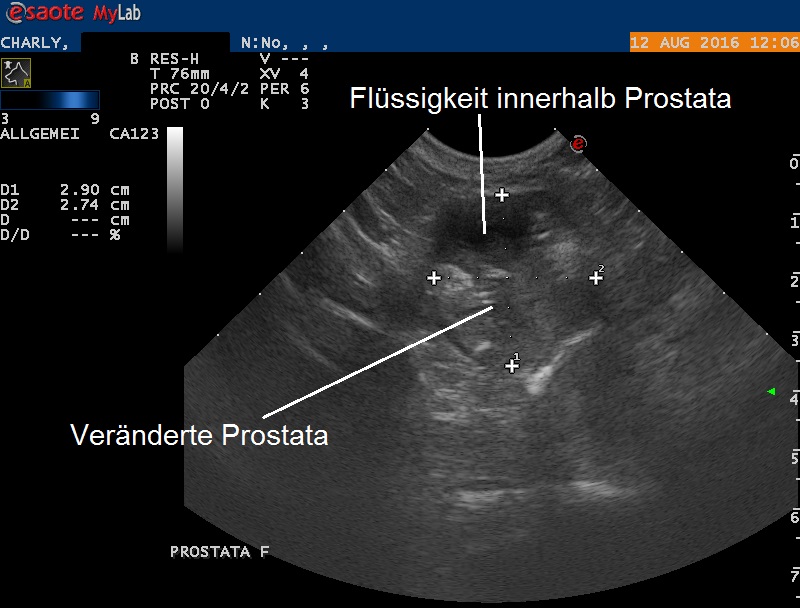

Anschliessend wird die Bauchhöhle mittels Ultraschall untersucht: Tatsächlich erscheinen die Beckeneingangs-Lymphknoten vergrössert. Die Prostata präsentiert sich vergrössert und mit stark variabler Echotextur; sie enthält einen flüssigkeitsgefüllten Hohlraum (zB Cyste oder Abszess) und stellenweise sind auch Verkalkungen zu sehen. Die Harnblase erscheint unauffällig.

In einem zweiten Untersuchungsschritt werden die Prostata und die vergrösserten Lymphknoten unter leichter Narkose unter Ultraschallführung punktiert: Die Prostatapunktion liefert etwa einen Milliliter einer bräunlich-roten, schleimigen, stark riechenden gallertigen Flüssigkeit. Nach der Punktion ist zu erkennen, dass die zuvor festgestellte Flüssigkeit in der Prostata komplett entfernt worden ist.